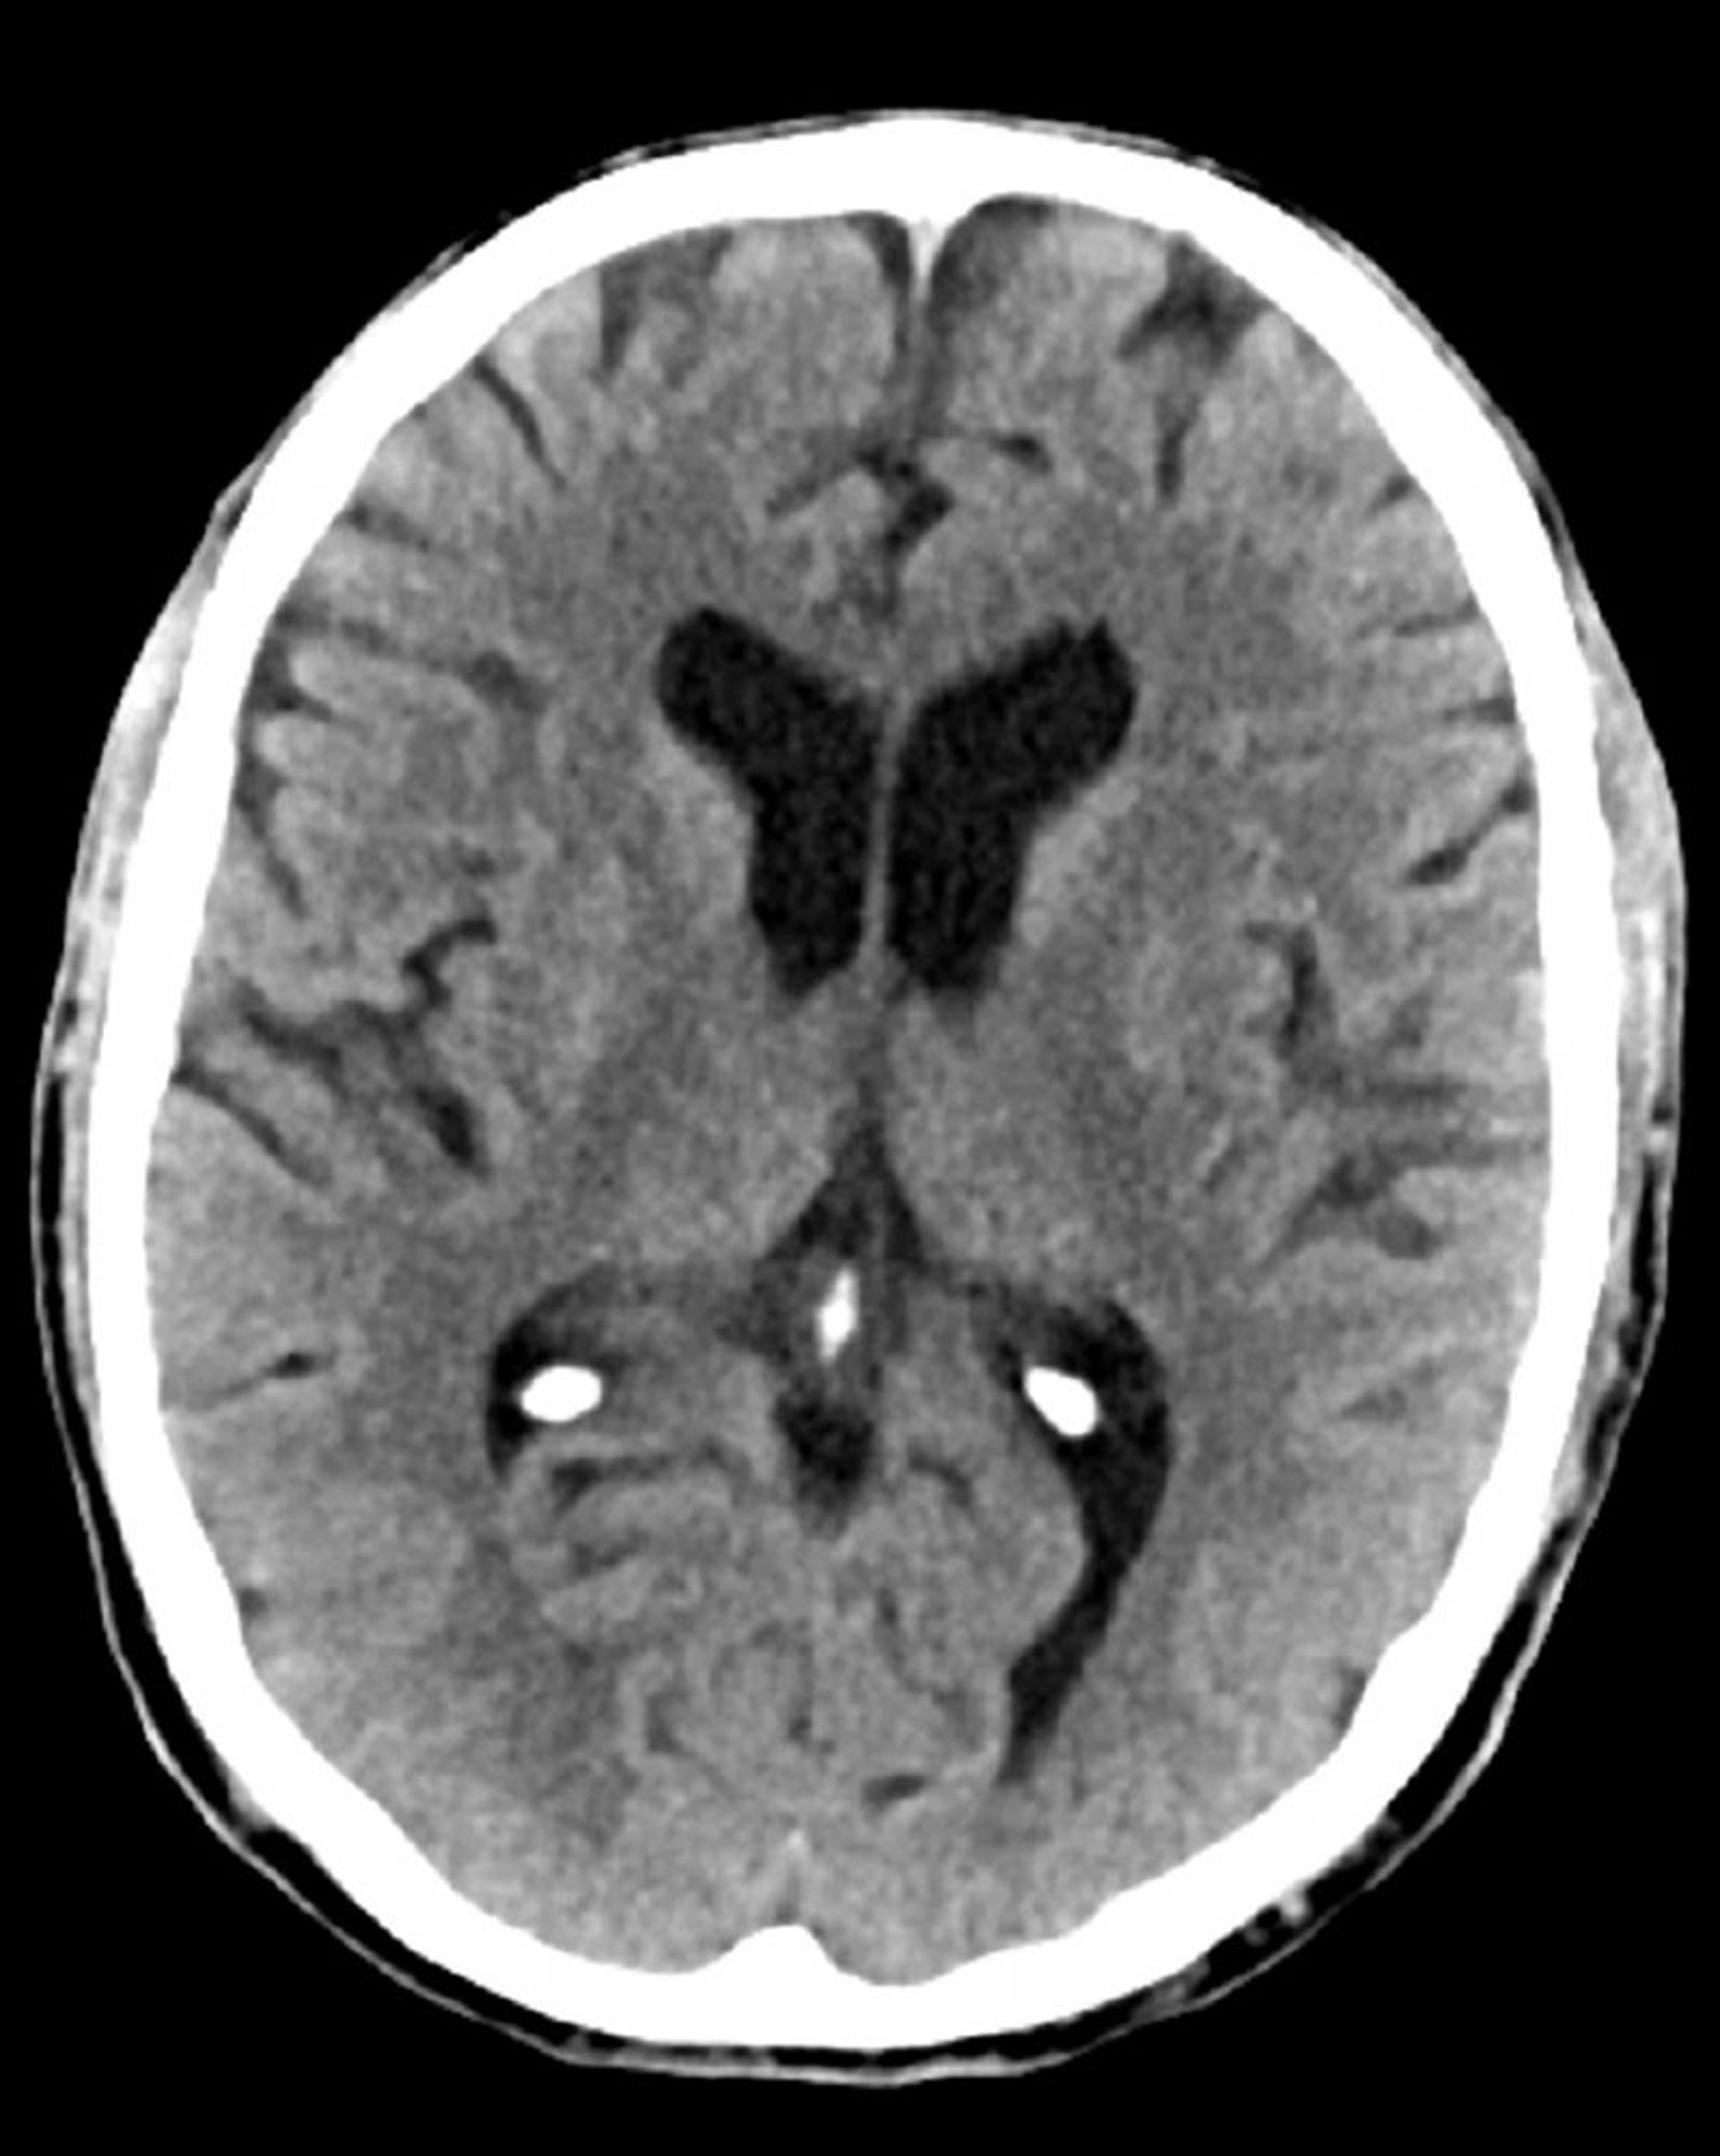

Tomodensitométrie normale de la tête (adulte, 74 ans) – Diapositive 5

Cette image est une TDM normale de la tête d'un adulte âgé de 74 ans. Par rapport à la TDM normale de la tête d'un patient de 30 ans, les ventricules et les sillons sont plus grands. Ces signes sont normaux dans ce groupe d'âge.